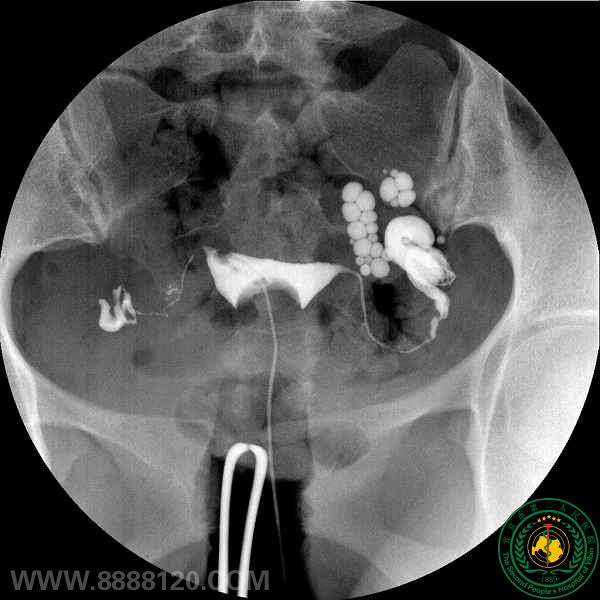

影像科介入病房开展输卵管再通术治疗不孕症

影像科介入病房开展输卵管再通术治疗不孕症2136